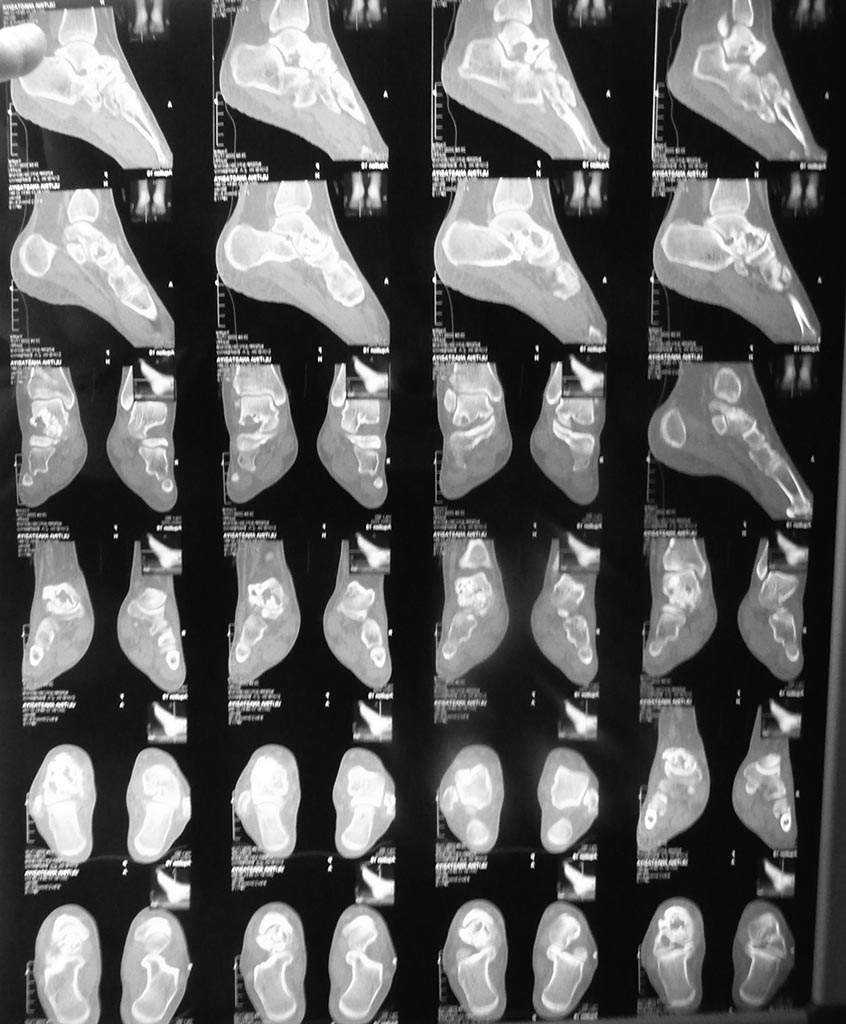

Здравствуйте, глубокоуважаемые участники форума. Прошу Вас о помощи в , на наш взгляд, не простом случае заболевания среднего отдела стопы у ребёнка 16 лет. Девушка имеет солитарную кисту головки и шейки таранной кости стопы. Обратилась и госпитализирована с болями в среднем отделе стопы. Ребёнок 16 лет. Направляющий диагноз: "Солитарная киста головки и шейки таранной кости стопы".Гистологический диагноз выставлен на основании пункционной биопсии в одной из авторитетнейших онкологических клиник Москвы. Выполненное лечение - инъекция Коллатампа - апрель 2017г. .

Ходит без ортеза. Жалуется на боли в области Шопарова сустава. Свод стопы сохранён. Тест "на носочках"-выполняет 15-20 секунд, жалуясь на возрастающие боли. Походка не нарушена. Может пройти 1 км пешком. Девушка крупного телосложения. Атрофии мышц голени нет. Пальпаторно - болезненность в области тыльной поверхности стопы в таранно-ладьевидного сустава. Движения в голеностопном суставе - в полном объёме. Результаты исследований будут в приложениях.

На КТ, вроде как, есть кисты и в области подтаранного сустава?

Тогда я за трехсуставной артродез. Костную пластику структурным аутотрансплантатом из крыла подвздошной, чтоб сверху кортикал остался. Уложить его в паз, с перекрытием таранноладьевидного.